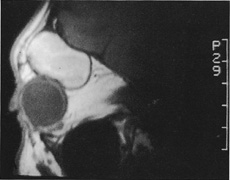

always can be extended farther posteriorly if exposure is inadequate.   Figure 10. A. Large, well-encapsulated intraconal mass on MR scan. B. Small lateral canthotomy incision will be used to perform lateral orbitotomy

and remove the intraconal mass.

Figure 10. A. Large, well-encapsulated intraconal mass on MR scan. B. Small lateral canthotomy incision will be used to perform lateral orbitotomy

and remove the intraconal mass.